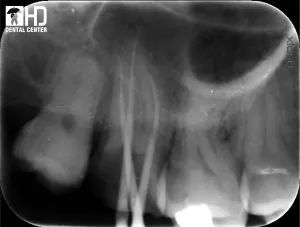

2/ Chữa tủy răng cối lớn hàm dưới

Đây là một ca điều trị tủy răng cối lớn hàm dưới, có cả 3 ống tủy đều bị cong. Chúng tôi đã sử dụng trâm Reciproc trong trường hợp này.